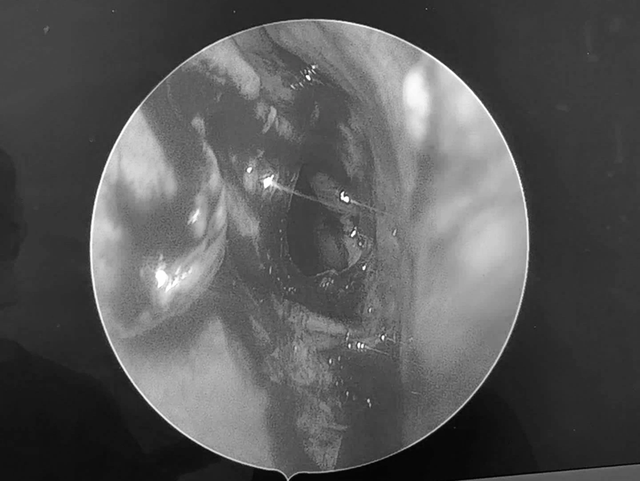

Sau khi thăm khám, bác sĩ Nguyễn Thanh Tiên cùng ê kíp đã tiến hành phẫu thuật mở xoang bướm và lấy sạch bệnh tích, dẫn lưu bằng phương pháp nội soi mũi xoang.